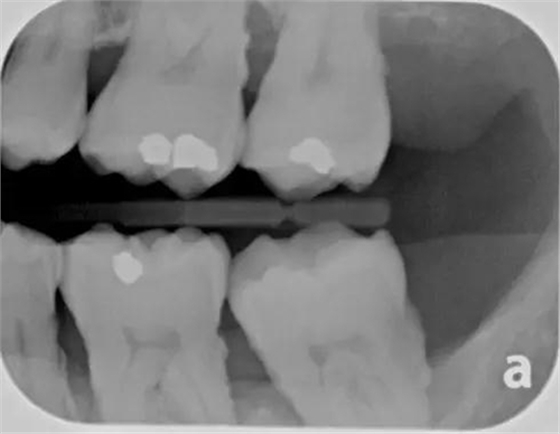

垂直咬翼片更適合牙周檢查。因?yàn)檠乐懿』颊咄ǔS泄俏眨绻諊?yán)重,水平咬翼片可能沒法顯示牙槽脊,而這時(shí)垂直咬翼片就顯示了其優(yōu)點(diǎn)。

另外,咬翼片在口腔里置放的位置所引起的圖像變形是最少的。當(dāng)然,它的不足之處是無法顯示根尖。所以,全口 X 光檢查包括根尖片和咬翼片,為的是取長補(bǔ)短。

圖 4 水平咬翼片,對有嚴(yán)重骨吸收的患者無法顯示牙槽脊(X 光片取自筆者治療過的病人)